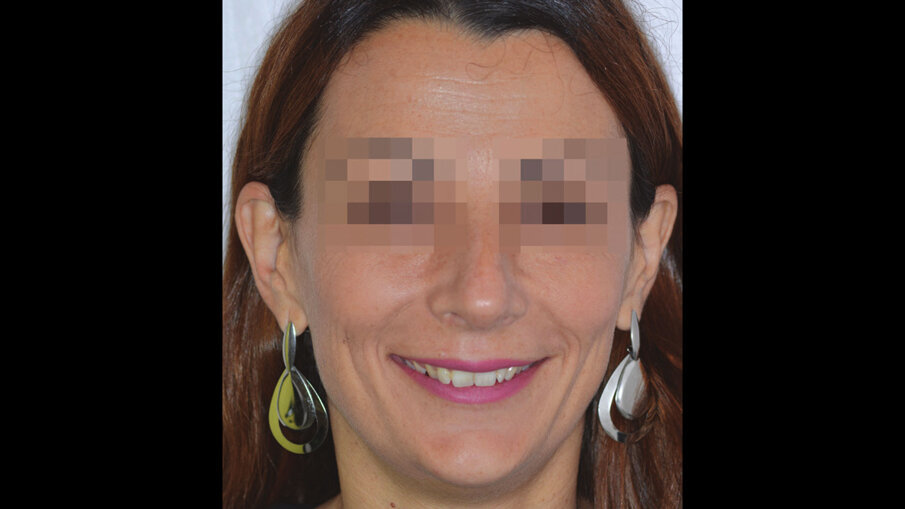

Figg. 4a-4c_Foto extraorali di inizio trattamento.

Figg. 4a-4c_Foto extraorali di inizio trattamento.

Figg. 4a-4c_Foto extraorali di inizio trattamento.